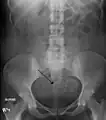

A very large (9 cm) fibroid of the uterus which is causing pelvic congestion syndrome as seen on CT

The presence of a uterine fibroid versus an adnexal tumor is made. Fibroids can be mistaken for ovarian neoplasms. An uncommon tumor which may be mistaken for a fibroid is Sarcoma botryoides. It is more common in children and adolescents. Like a fibroid, it can also protrude from the vagina and is distinguished from fibroids.[8] While palpation used in a pelvic examination can typically identify the presence of larger fibroids, gynecologic ultrasonography (ultrasound) has evolved as the standard tool to evaluate the uterus for fibroids. Sonography will depict the fibroids as focal masses with a heterogeneous texture, which usually cause shadowing of the ultrasound beam. The location can be determined and dimensions of the lesion measured. Also, magnetic resonance imaging (MRI) can be used to define the depiction of the size and location of the fibroids within the uterus.

Imaging modalities cannot clearly distinguish between the benign uterine leiomyoma and the malignant uterine leiomyosarcoma, however, the latter is quite rare. Fast growth or unexpected growth, such as enlargement of a lesion after menopause, raise the level of suspicion that the lesion might be a sarcoma. Also, with advanced malignant lesions, there may be evidence of local invasion. A biopsy is rarely performed and if performed, is rarely diagnostic. Should there be an uncertain diagnosis after ultrasounds and MRI imaging, surgery is generally indicated.

Other imaging techniques that may be helpful specifically in the evaluation of lesions that affect the uterine cavity are hysterosalpingography or sonohysterography.